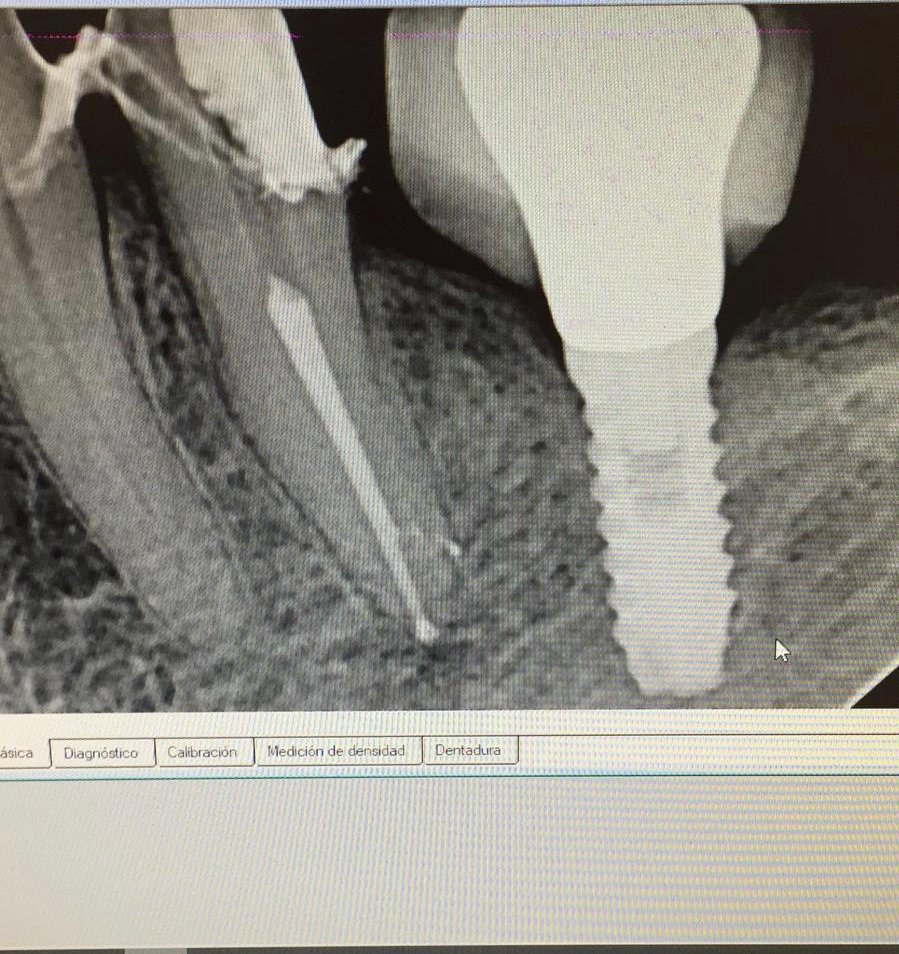

Que implante es el 36?

Buenas tardes compañeros. Acudo a vosotros para ver si me podéis ayudar. Sabríais decirme marca y modelo? Gracias!